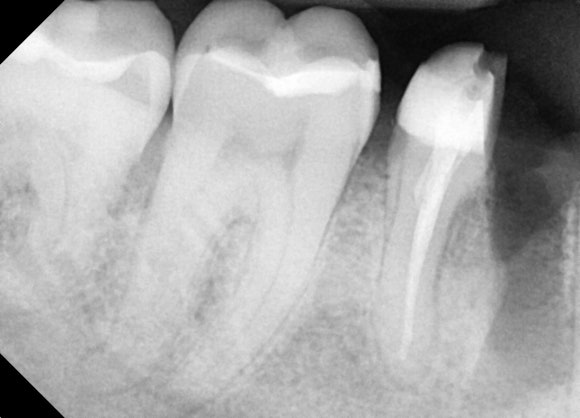

20250627

뿌리 하나를 남기고,

머리 부분은 깨끗하게 정돈하였습니다.